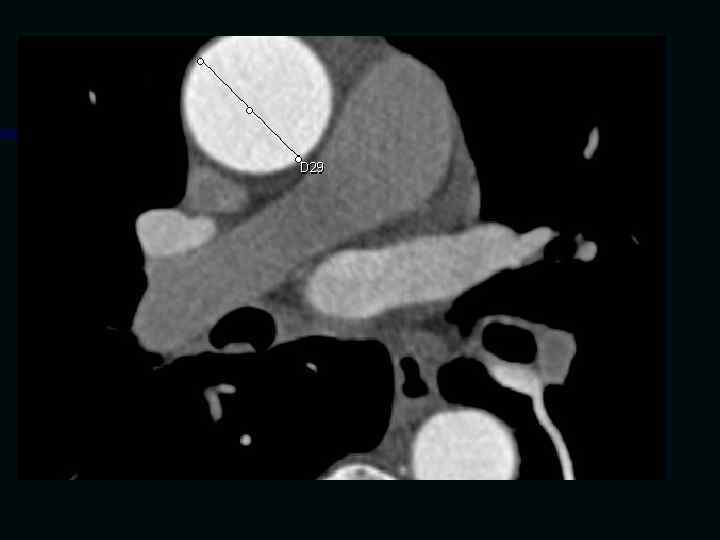

Исследование сосудов грудной клетки